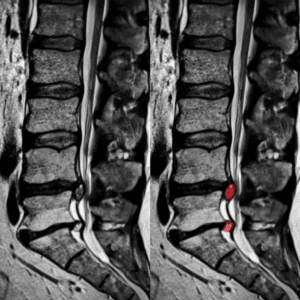

Imaging for Sciatica

MRI: An MRI provides detailed 3D images of soft tissues, making it an essential tool if there is concern about more serious conditions, such as tumours or trauma-related injuries.

Please note that if you are having a spinal injection, then you will need to have an up to date MRI scan that has been done within the last 6 months. We can help arrange these for you if they are required – you don’t need to have a GP referral.

Ultrasound-guided spinal injections are a minimally invasive procedure used to manage sciatica, As previously discussed, sciatica may result from herniated discs, spinal stenosis, or other degenerative conditions.